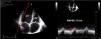

All prosthetic valves create a certain degree of obstruction compared to native valves depending on their design, size, and annular position (intra/supra), resembling stenosis. It is advisable to consult expected gradients for the diameter and model of the prosthesis (appendices 1 and 2).31–35 Therefore, it can be difficult to differentiate hemodynamic obstruction from a mild pathological dysfunction and prosthesis-patient mismatch (PPM) or mismatch (Table 3, Fig. 4, video 4 of the supplementary data).36

In the aortic position, the triangular morphology of the Doppler velocity contour with a short acceleration time provides us with information of normal functioning. As obstruction progresses, the Doppler velocity contour will become more rounded, until it reaches a delayed peak flow (Fig. 4).

Figure 4.* Pulsed-wave Doppler sample volume very close to the prosthesis. # Stenosis additionally confirmed by the EOA compared with reference values if valve type and size are known. ** Pulsed-wave Doppler sample volume distant (apical) from the prosthesis. AT, acceleration time; DLVOT, diameter of the LVOT; DVI, Doppler velocity index or nondimensional functional index; EOA, effective orifice area; indexed EOA, EOA divided by body surface area; LVOT, left ventricular outflow tract; PPM, prosthesis-patient mismatch; VTI, velocity-time integral.

Modified from Zoghbi WA, et al.